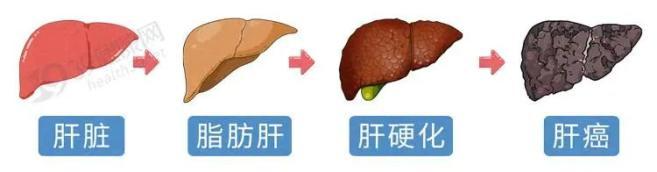

2023年发布的一项针对中国575万余份体检的分析研究发现,脂肪肝、重度脂肪肝的患病率分别为44.39%、10.57%。不加以控制的话,脂肪肝会逐渐演变成脂肪性肝炎、肝纤维化、肝硬化,乃至肝癌。

美国肝病研究学会在《肝病学》上发表的一项研究也指出,脂肪肝会让肝脏长期处于炎症状态下,容易引起肝细胞癌变。且这些患者身上多伴有代谢综合征,会促进其他部位发生癌症,会给身体带来全方位的伤害,给癌症的发生提供“温床”。

如若是急性脂肪肝的话,还有起病急、进展快、病情重的特点,严重的情况下会在数小时、数天让多器官衰竭,致死率高达60%。